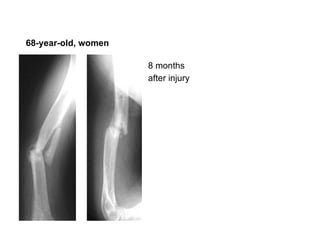

8 months after injury   68-year-old, women

68-year-old, women